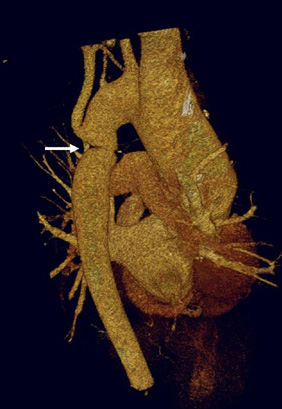

Three-dimensional computed tomographic reconstruction visualized from posterior to anterior. The area of coarctation is well seen (arrow)

From the personal collection of Jeffrey Gossett, MD, Children's Memorial Hospital, Northwestern University, Chicago; used with permission